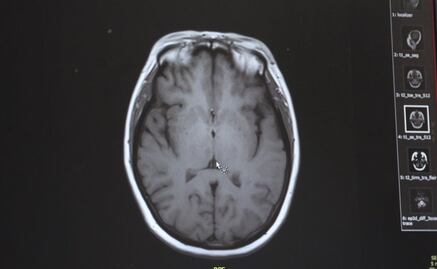

El 11 de septiembre, los habitantes de este municipio del sur de Estados Unidos se despertaron con la noticia de que un menor de edad había fallecido debido a una extraña " ameba come cerebros ".

Por lo que se ha podido conocer, ese peculiar parásito le ocasionó una infección cerebral que, tras ser hospitalizado el 5 de septiembre, desencadenó su muerte poco más de cien horas después.